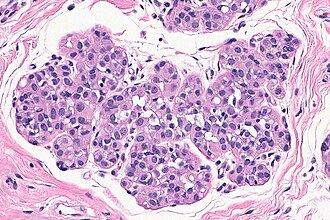

Template:Px Atypical lobular hyperplasia. H&E stain. (WC/Nephron) | |

| LM | morphologic changes (atypia minimal - usually, borders of cells distinct/visible - dyscohesive, clear cytoplasm (focal), distend duct, eccentric nucleus, usu. round, filled ducts (no luminal spaces - key feature), limited extent (<50% of terminal duct lobular unit is involved) |

| LM DDx | lobular carcinoma in situ, lobular carcinoma |

| IHC | E-cadherin -ve |

Atypical lobular hyperplasia, abbreviated ALH, a pre-malignant change in the breast characterized by cellular proliferation and cellular dyscohesion.

It can be seen as the precursor to lobular carcinoma in situ, the precursor of lobular carcinoma.

- Atypia minimal - usually.

- Relatively small ~1-2x size lymphocyte.

- Borders of cells distinct/visible - dyscohesive.

- Clear cytoplasm (focal).

- May have a signet ring cell-like appearance.

- Distend duct.

- Eccentric nucleus, usu. round.

- Filled ducts.

- No luminal spaces - key feature.

- Limited extent: <50% of terminal duct lobular unit (TDLU) is involved.